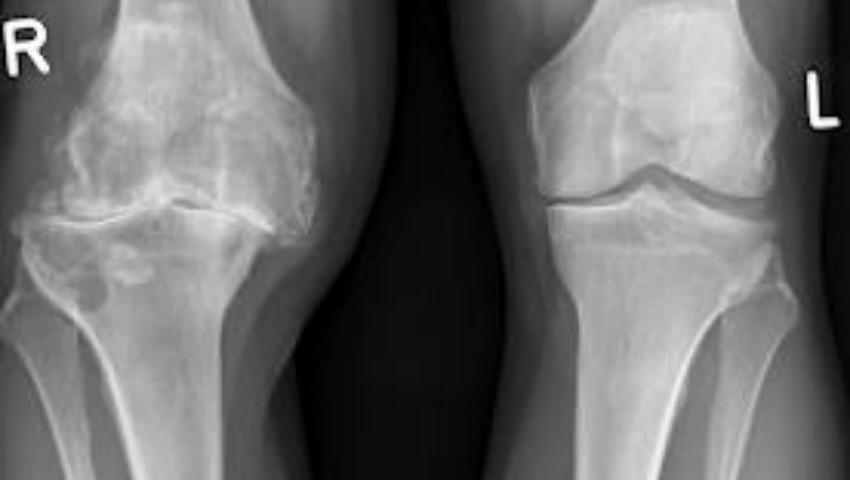

Pentru prima dată în Moldova, chirurgii de la Institutul de Urgență au implantat proteze în genunchi, folosind un sistem de navigare computerizat. Noul tip de intervenție permite că pacientul să piardă de două ori mai puțin sânge și să se recupereze mai rapid.

Mai exact, chirurgii au reușit să implanteze proteze la genunchi, fiind ghidați cu o precizie de milimetri, de un sistem de navigare, scrie protv.md.Astfel, spre deosebire de metodă folosită anterior, acum chirurgii pot vedea pe monitor zona de protezare și pot urmări orice mișcare pe care o fac în timpul intervenției. Nouă operație permite că proteză să fie implantată mai solid și cu mai multă exactitate.Prima intervenție de acest fel a suportat-o o femeie, de 65 de ani, care suferea de artroză de genunchi avansată. Totul a decurs cu succes, povestesc specialiștii, iar pacienta a fost deja externată. În timpul protezării genunchilor cu ajutorul sistemului de navigare, pacientul pierde de două ori mai puțîn sânge și se recuperează mai repede.În lume, asemenea intervenții au început să fie făcute încă acum aproximativ 7 ani.Pentru a folosi aceleași tehnici că și în străinătate, patru medici de la noi au plecat la un training în Franța. Utilajul necesar a apărut la Insitutul de Medicină Urgență prin donații. Până acum, chirurgii au efectuat 7 intervenții de protezare a genunchilor cu sistem de navigare. Persoanele care au nevoie de asemenea operație, se pot adresa la medici pentru consultații și, ulterior, vor fi incluși în lista de așteptare. Operația este gratuită pentru pacienții care au polița medicală. Cheltuielile sunt acoperite de Compania Națională de Asigurări în Medicină și variază între 40 și 150 de mii de lei, în dependență de complexitatea operației.